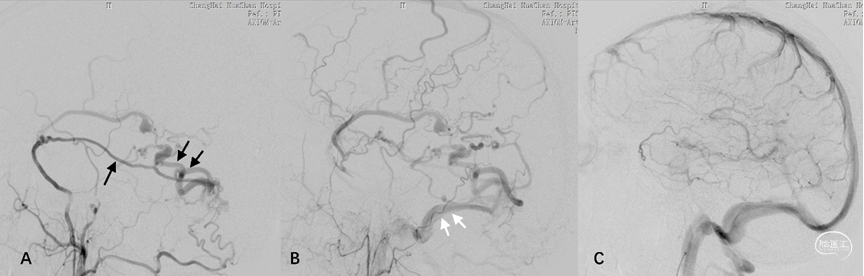

2.桥静脉型硬脑膜动静脉瘘(bridging vein type DAVF, BV-DAVF),即动-静脉移行起自硬膜固有静脉,经桥静脉硬膜内段向软膜静脉逆流。由于桥静脉向静脉窦直接引流受阻,动静脉瘘无法直接进入静脉窦,而通过侧枝吻合进入邻近静脉窦。影像学表现为桥静脉-软膜静脉早显,并早于静脉窦显影(图3)。

图3. 桥静脉型DAVF的血管构筑。侧窦区桥静脉型DAVF的起点位于桥静脉硬膜内段,由MMA(黑箭)供血,向软膜静脉逆流(A)。同侧乙状窦(双白箭)晚于桥静脉-软膜静脉间接显影(B)。脑静脉窦期显示静脉窦血流通畅,侧裂浅静脉回流被DAVF竞争性抑制(C)